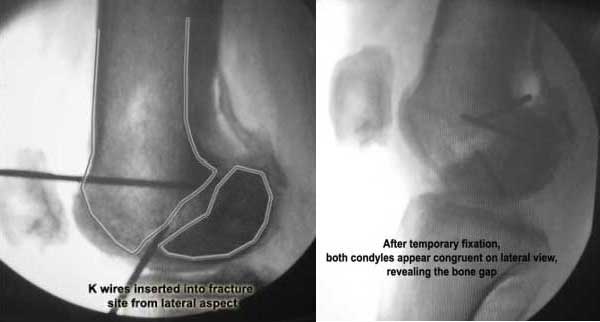

This 20 year old patient sustained a fracture in the lower end of the femur, one and a half years ago, with a compound wound over the fracture area. Notes at that time mention a compound fracture dislocation, with a loss of part of the lateral condyle. This was treated by debridement, and external fixation. After two weeks, the lateral condyle (coronal fracture) was fixed by a screw and k wire in an AP direction.

I cannot make certain from the AP whether the screw and KW are still present. The lateral however shows that the lateral condyle was fixed with disregard to the bone defect. So it was proximally displaced in relation to the medial condyle with the resultant valgus. I would do an open wedge osteotomy with bone graft and internal fixation. However, this would require a precise estimate of the correction angle and placement of the fixation device. I would use a DCS.

I opened it up from the lateral aspect.

Freed up the non-union site with minimal disturbance to the posterior and lateral soft tissue attachments on the lateral condyle fragment.

Applied a distractor between femoral shaft and tibia, to create a space on the lateral aspect.

This brought the lateral condylar fragment into a position that seemed to be reasonably well aligned, but showed up a bone gap.

This was fixed temporarily, bone grafted with tricortical struts, and fixed by two cancellous screws. The fragment was not large enough to afford any fixation to a plate or such implant, and the screws held it compressed well to the rest of the distal femur.